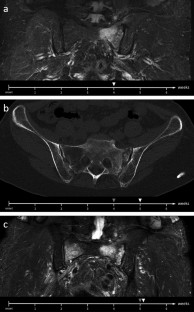

Fig. 1

Fig. 2

Fig. 3

Fig. 4